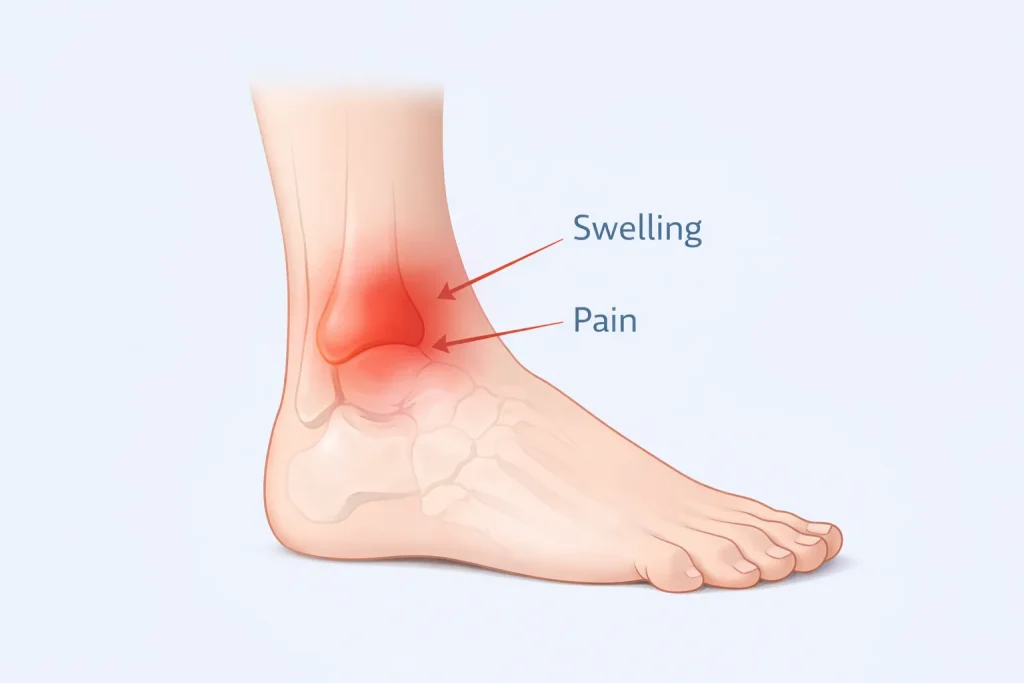

Symptoms of Medial Malleolus Fracture

Symptoms typically appear immediately after injury but may vary depending on severity.

Common symptoms include:

- Pain on the inner side of the ankle

- Swelling around the ankle joint

- Bruising or discoloration

- Difficulty bearing weight

- Tenderness when touching the inner ankle

- Reduced range of motion

In severe fractures, visible deformity or inability to stand may occur. Persistent pain after an ankle injury should always be evaluated with imaging.